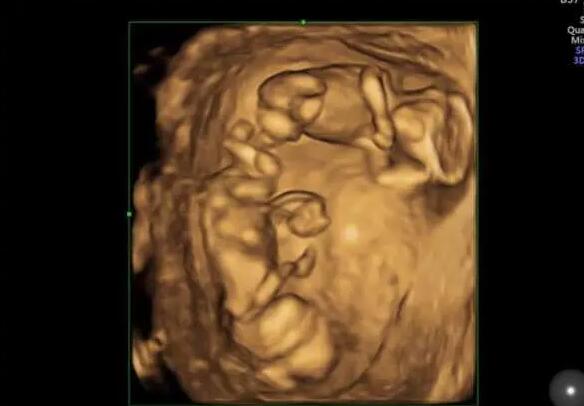

揭秘试管移植双胎全过程!从胚胎培养到成功着床的关键步骤

2026-01-21